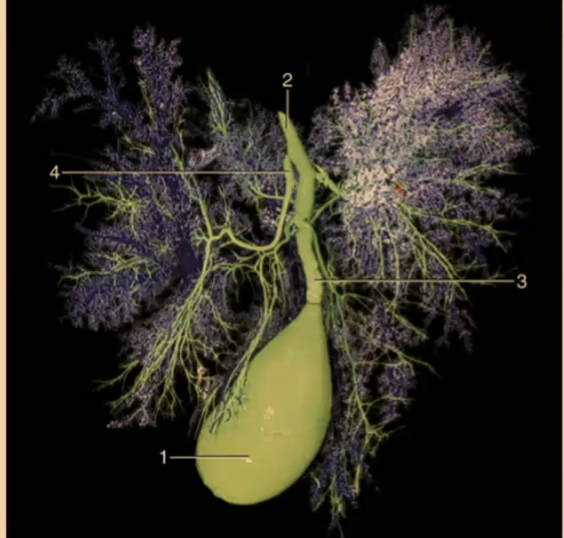

How many lobes are there to the liver?

4

What are the 4 lobes of the liver?

Left, Quadrate, Right, Caudate

#2?

Medial

#1?

Lateral

#3?

Quadrate

#4?

Medial

#5

Lateral

#6 & #7

Caudate

What produces bile?

Liver

#2

Bile duct

#1

Gallbladder

What animal is there no gallbladder?

Horse

Where is the bile stored?

Gallbladder